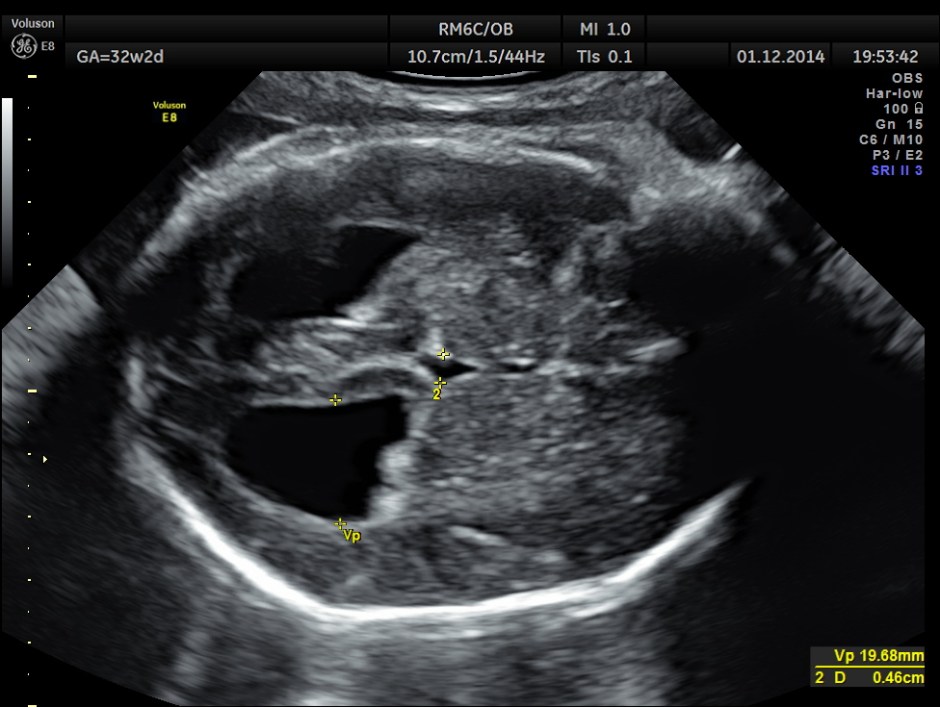

3D view of the same.